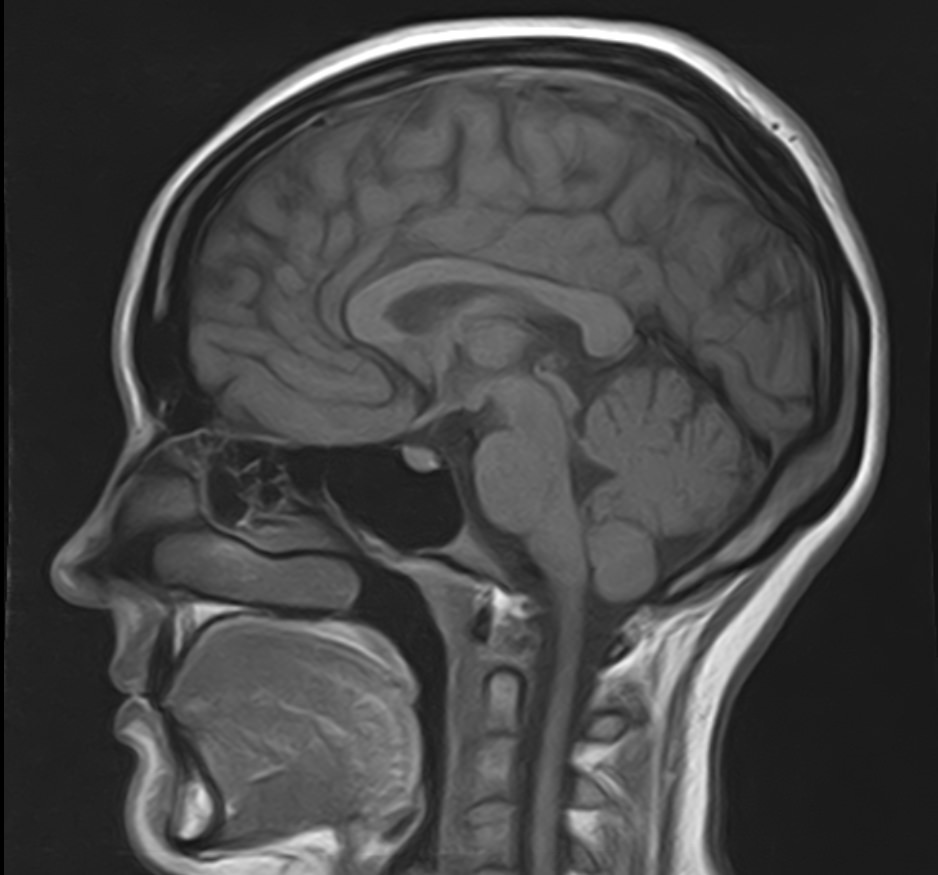

К центральной нервной системе организма относится головной мозг, расположенный в полости черепа, и спинной мозг, проходящий в спинномозговом канале позвоночного столба. В головном мозге находятся высшие центры управления всем организмом, спинной мозг имеет двусторонние связи с ними, то есть является проводником импульсов от периферии к головном мозгу и обратно.

Патология ЦНС может проявляться многообразной неврологической симптоматикой, в зависимости от уровня поражения. Причинами ее появления могут быть травматические повреждения, проникновение инфекции, демиелинизирующие и дегенеративные заболевания, сосудистая патология, опухолевые процессы.

Для диагностики заболеваний ЦНС в клинике «Доступная медицина» проводится комплексное обследование МРТ ЦНС (центральной нервной системы). Клиника укомплектована высокотехнологичным оборудованием, в частности, новейшим 32-канальным высокопольным томографом TOSHIBA VANTAGE TITAN 1,5 Тесла с высокой разрешающей способностью для точной диагностики заболеваний центральной нервной системы.

Комплексное обследование ЦНС выполняется как в стандартном режиме, когда не применяется использование контраста, так и с контрастным усилением. Для более точной диагностики некоторых патологий головного и спинного мозга внутривенно вводится контрастное вещество. С помощью контраста можно обнаружить опухолевые образования размером от 1 мм, демиелинизирующие процессы, дегенеративно-дистрофические заболевания, воспалительные процессы, сосудистую патологию.